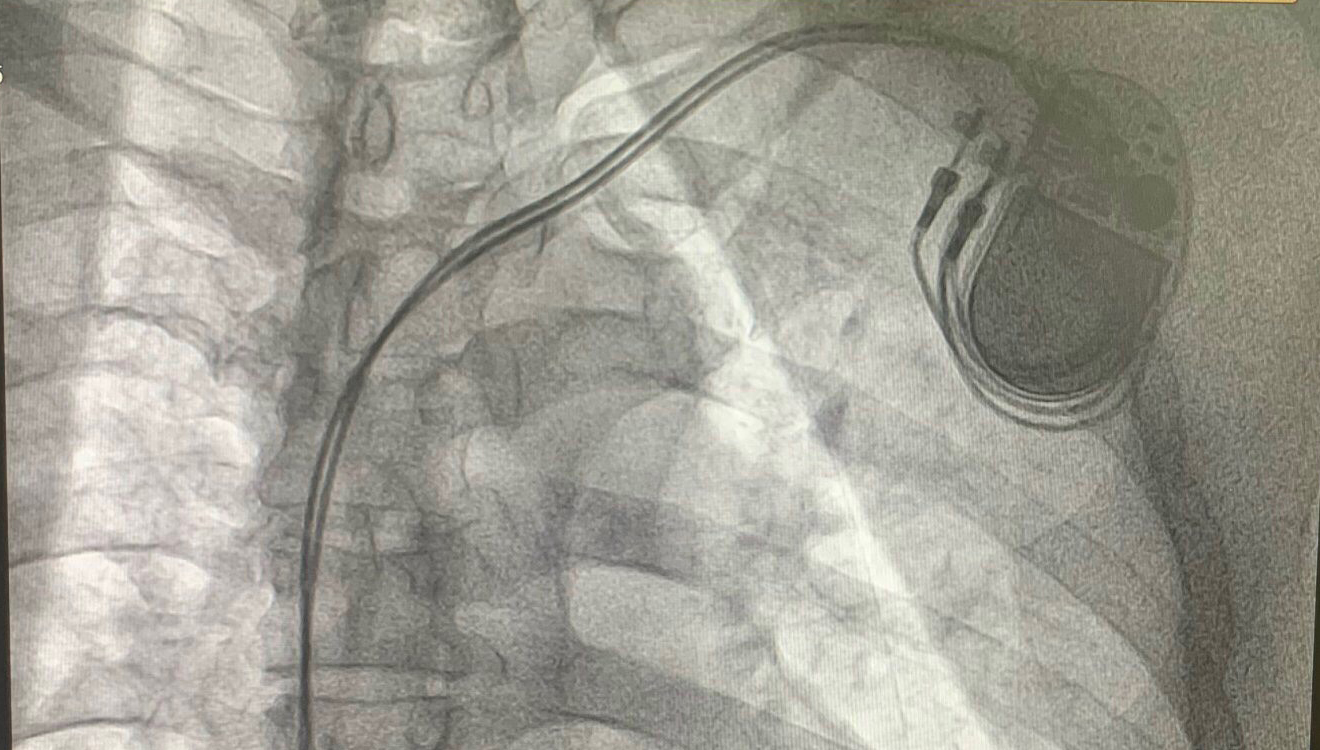

Hình ảnh máy tạo nhịp được cấy an toàn vào buồng tim người bệnh